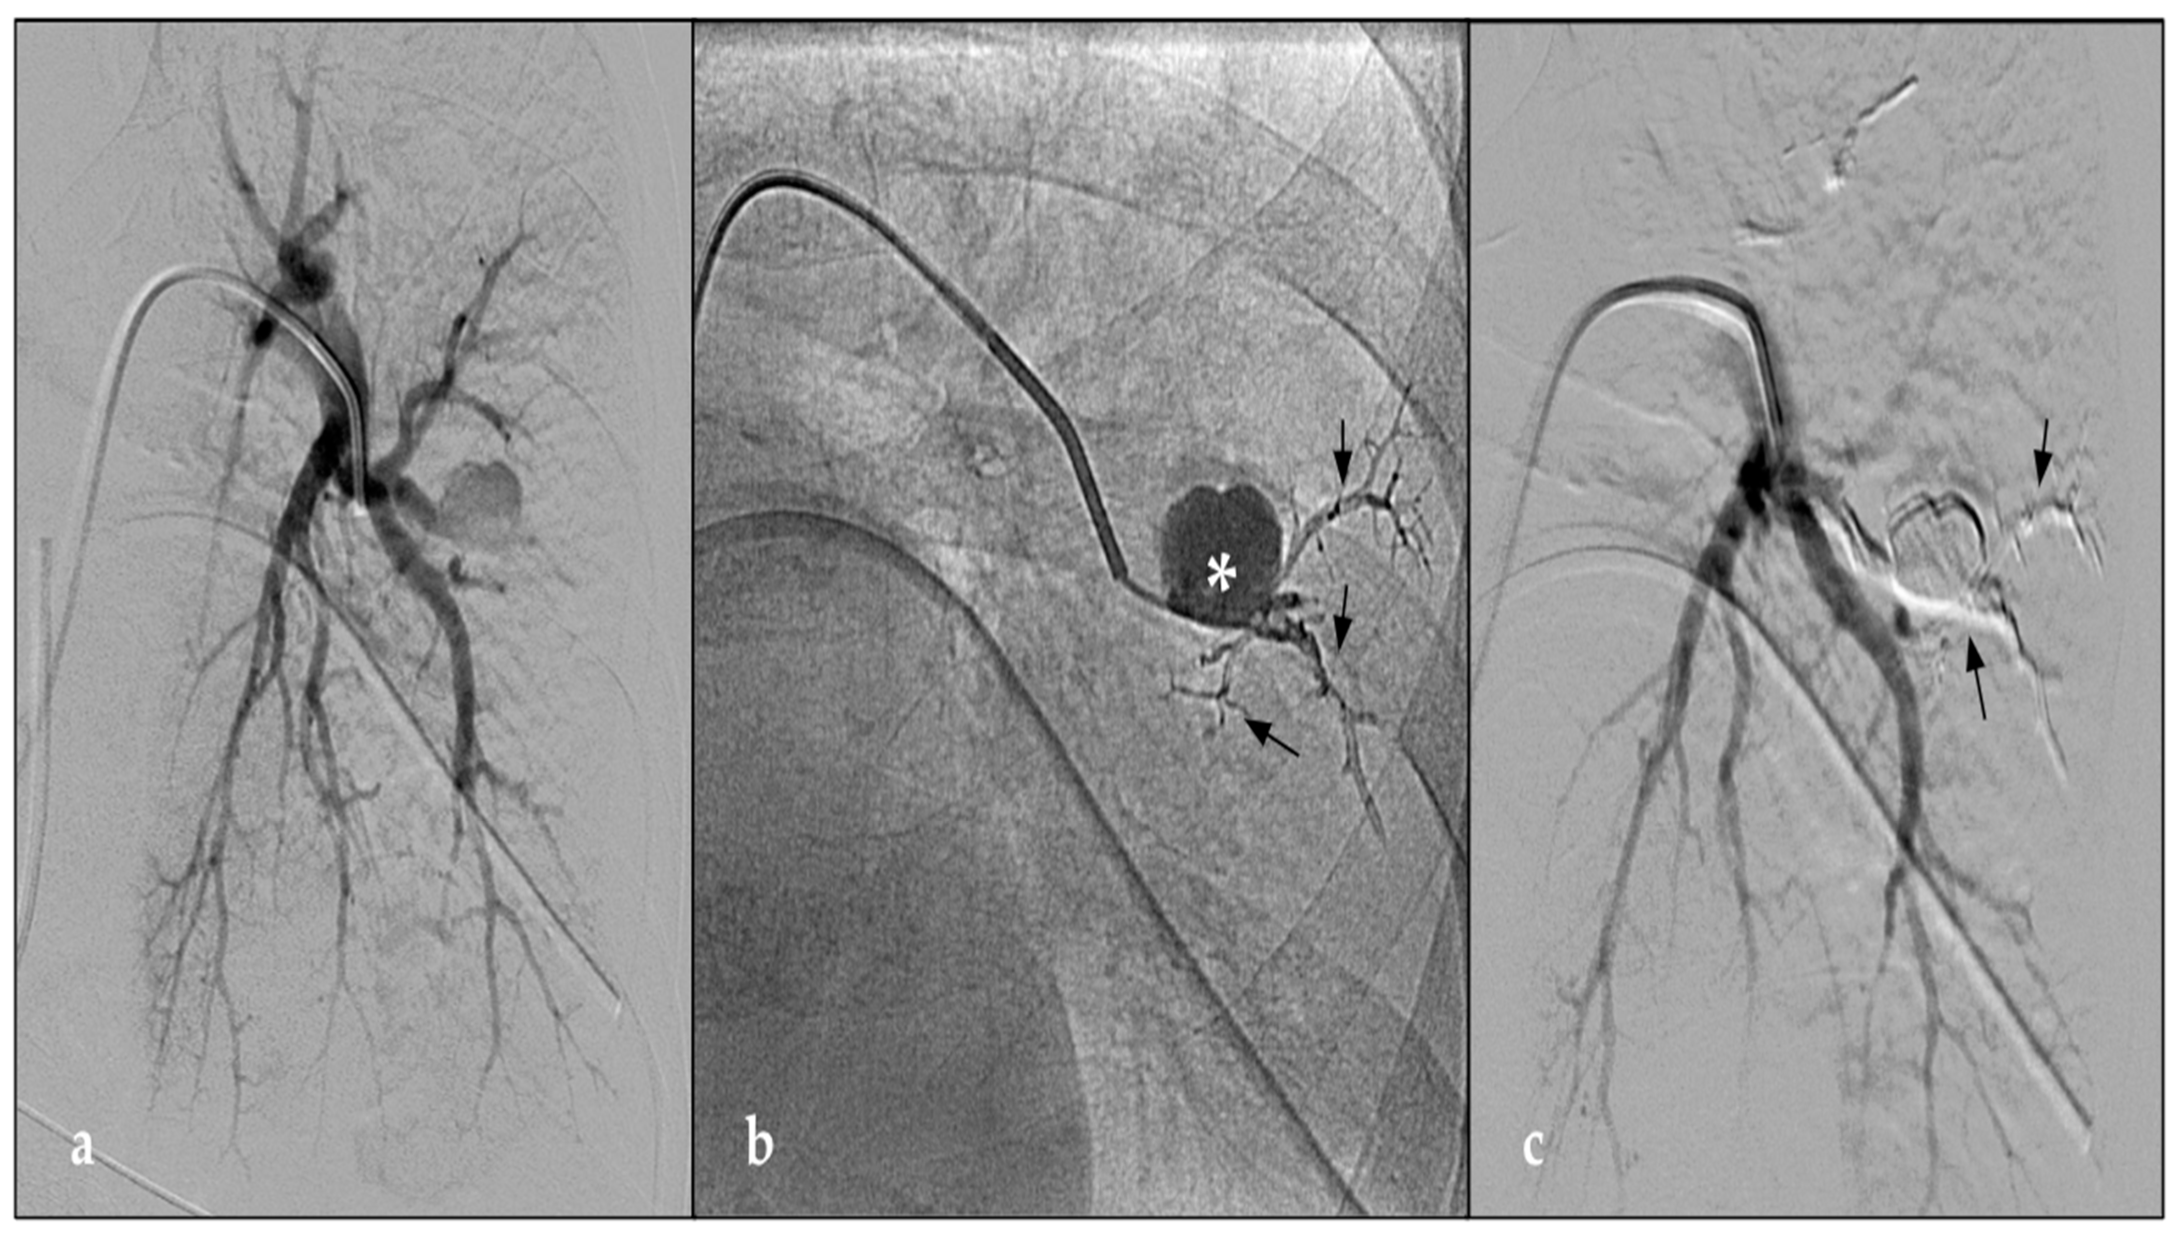

| 1 | M | 73 | Swan-Ganz | Right Lower lobe | CTA | CTA | Coils and Glue | No PAPA revascularization |

| 2 | F | 35 | Fall from horse | Left Lower lobe | CTA | CTA | Coils | No PAPA revascularization |

| 3 | F | 65 | Swan-Ganz | Right Medium lobe | CTA | CTA | Vascular plug and Glue | No PAPA revascularization |

| 4 | F | 72 | Swan-Ganz | Right Lower lobe | CTA | CTA | Coils | No PAPA revascularization |

| 5 | F | 75 | Swan-Ganz | Right Medium lobe | CTA | CTA | Coils | No PAPA revascularization |

| 6 | M | 56 | Car accident penetrating trauma | Right Lower lobe | CTA | CTA | Coils and AEA | No PAPA revascularization |

| 7 | M | 48 | Temporary pacemaker | Left Lower lobe | Thoracic X-ray | CTA | Coils and EVOH liquid | No PAPA revascularization |

| 8 | F | 72 | Swan-Ganz | Left Lower lobe | CTA | CTA | EVOH liquid | No PAPA revascularization |